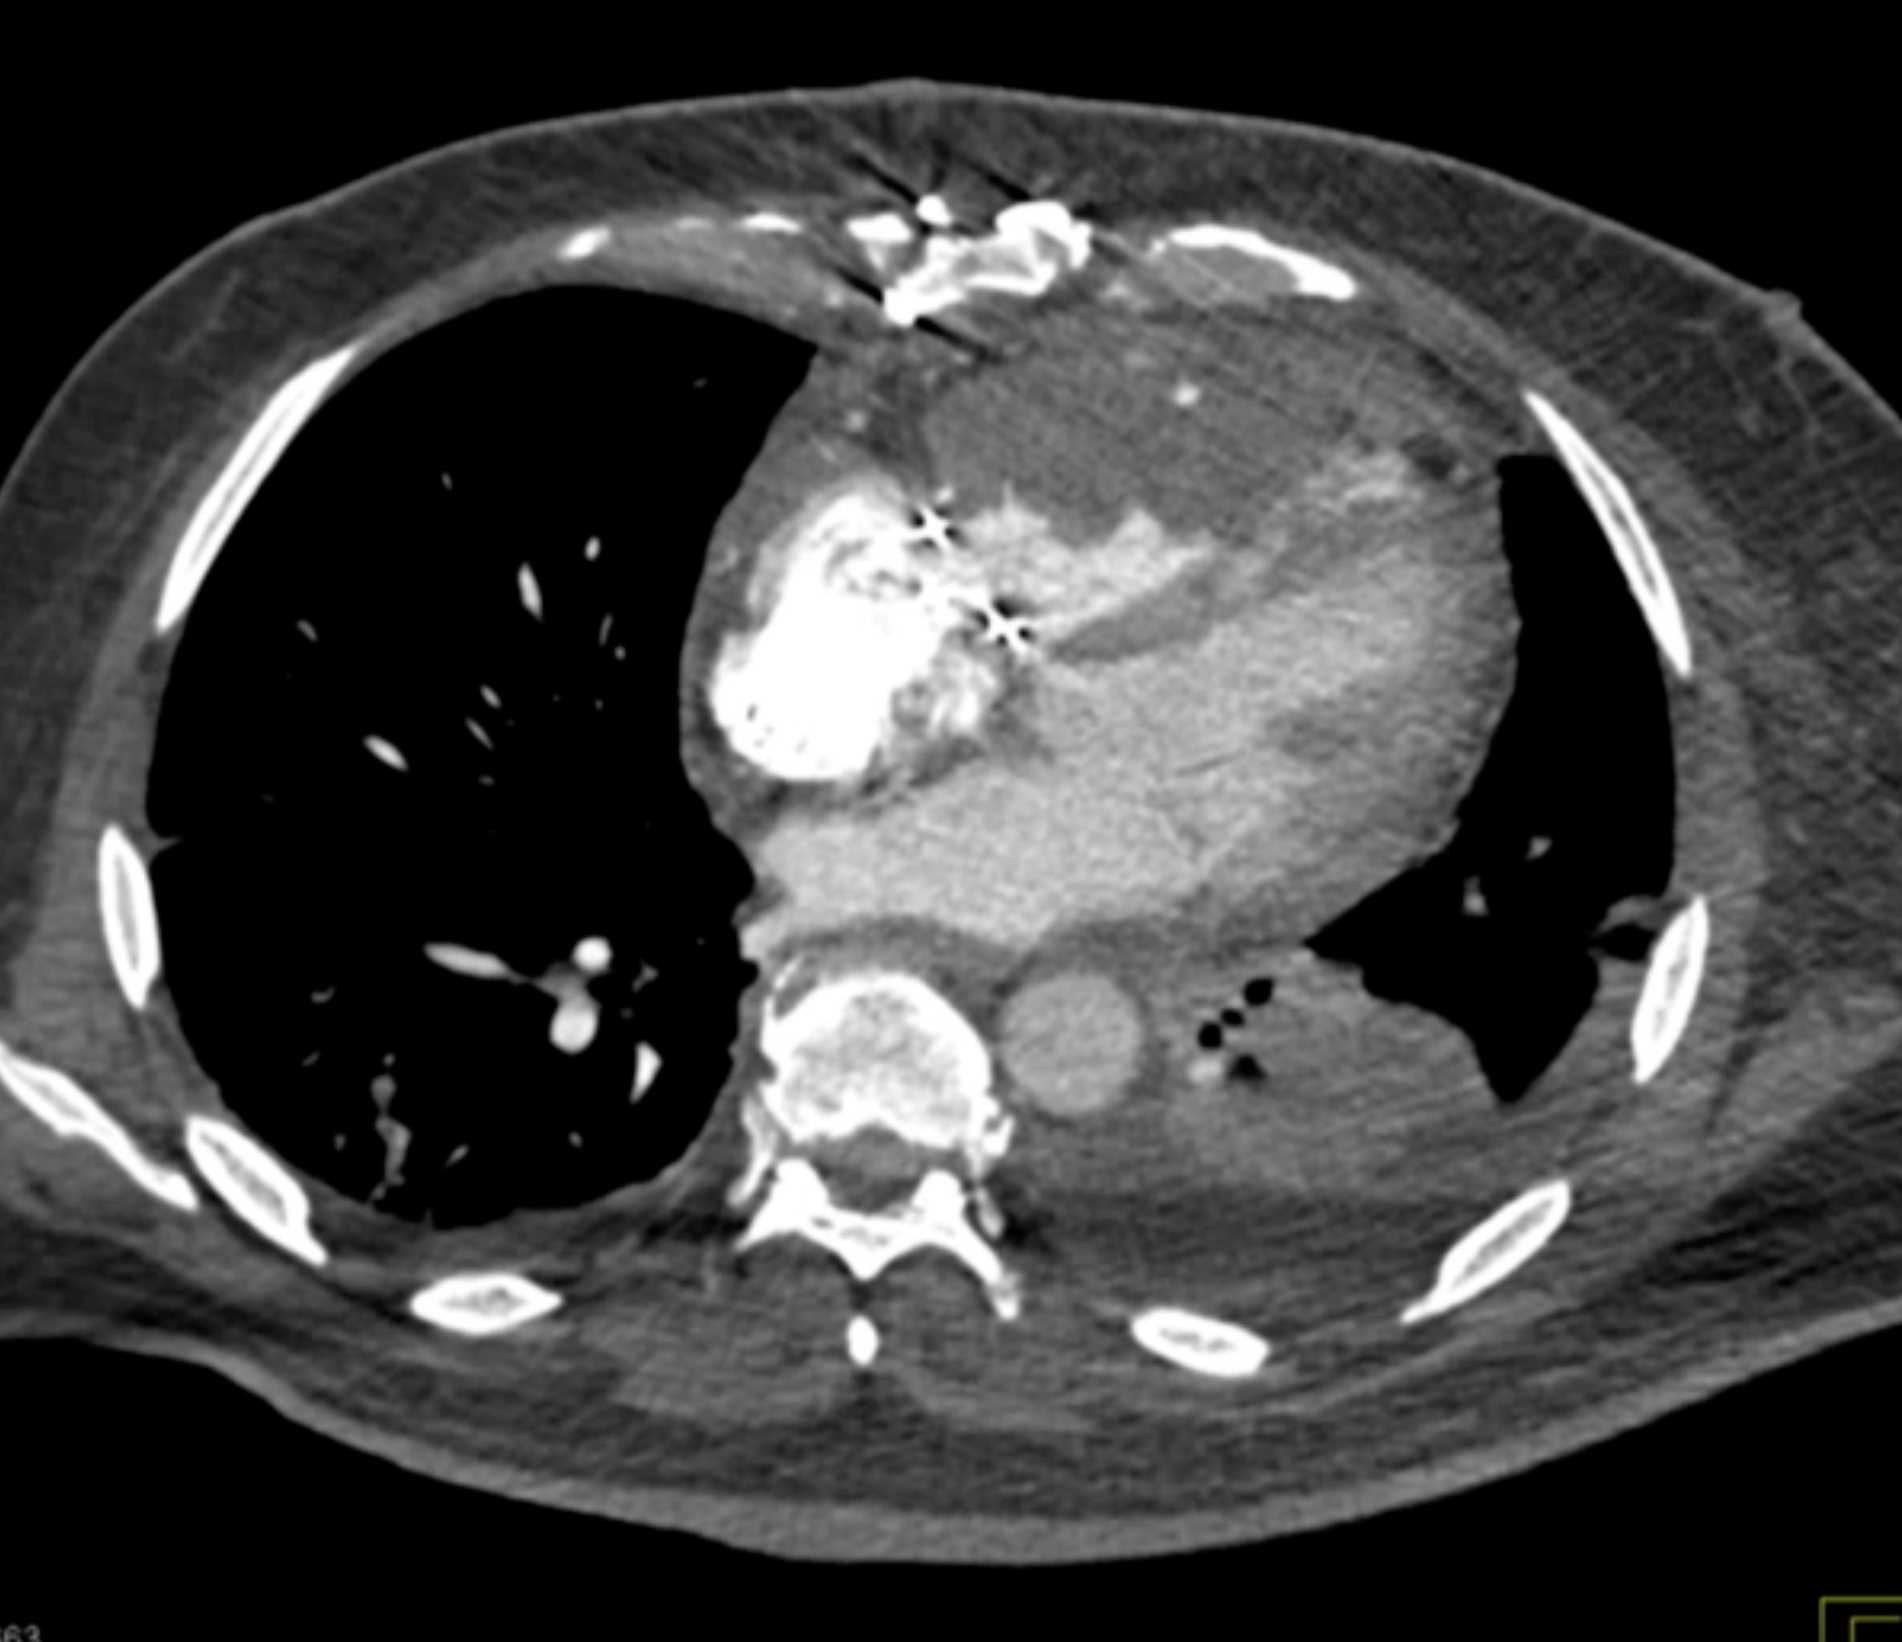

Primary Spindle Cell Carcinoma of the Right Ventricle